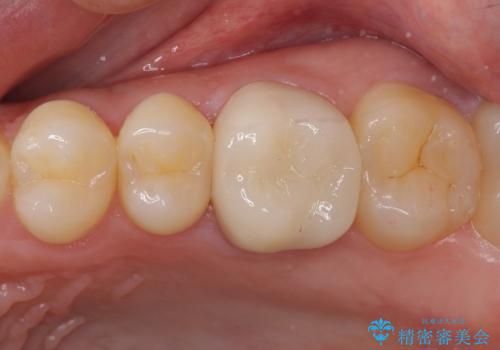

[根管治療・セラミッククラウン] 他院で抜くしかないと言われた歯の治療

![[根管治療・セラミッククラウン] 他院で抜くしかないと言われた歯の治療の症例 治療後](https://seimitsushinbi.jp/wp/wp-content/uploads/2021/01/08b00294d18b426c4a403cba0a149a80-500x350.jpg?v=1609913645)